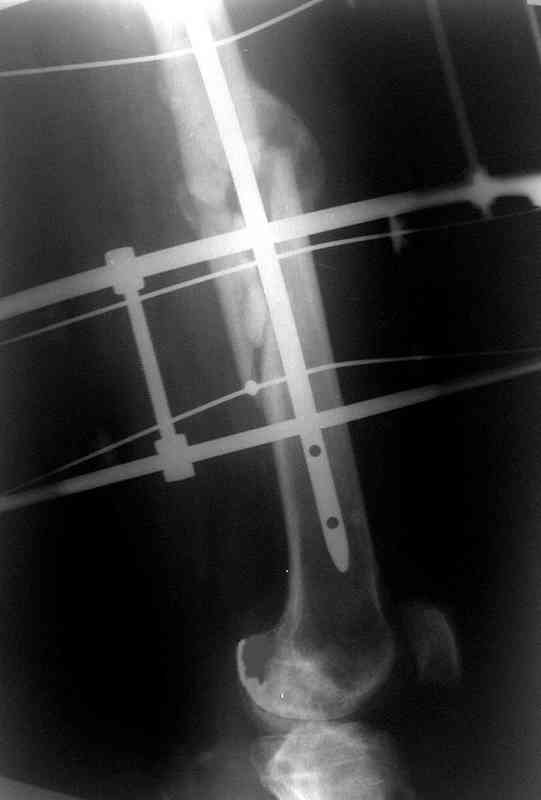

Сувалян Микаэл 01 Апрель 2007, 14:01

Вчера, когда написал свое сообщение, решил еще раз открыть фоторентгенограмму и убедиться в правильности своих суждений на счет общепринятого интрамедуллярного остеосинтеза. Попытка была безуспешна:)

Сегодня фотография открылась...беру свои слова назад: перелом явно в расширенном участке бедра. Целесообразней всего динамический блокирующий остеосинтез.

Ротации конечности у больного нет?

Учитывая смещения отомков по длине (хоть и 1,5 см, но все же..), очевидное ротационное смещение (видно даже по Р-мам) самым правильным, на мой взгляд, решением было бы: наложение аппарата Илизарова на бедро с остеотомией бедренной кости и исправлением ротационной деформации. Дистракция на аппрате пару недель и последующий блокирующий остеосинтез. У нас в клинике был один пациент с практически идентичной историей (укорочение конечности было значительно больше), которому мы выполнили такую операцию (блокирующий остеосинтез был выполнен без рассверливания костно-мозгового канала). В настоящее время больной работает, прыгает с парашютом, периодически звонит и благодарит за лечение.

История больного, о котором я говорил выше. Не удивляйтесь изложенному

материалу (выдержка из диссертационной работы).

Больной А., 28 лет, поступил в НИИ им. Н.В. Склифосовского 22.12.99 после падения на улице. Жалобы на боли в области левого тазобедренного сустава и левом бедре. Из анамнеза следовало, что 20.06 во время прыжка с парашютом у него возник закрытый оскольчатый перелом средней трети левой бедренной кости со смещением отломков, по поводу чего в одной из ЦРБ Московской области через 3 дня после травмы был произведен открытый интрамедуллярный остеосинтез штифтом типа Кюнчера.

Послеоперационное течение было гладким. Больной ходил при помощи костылей с дозированной нагрузкой на оперированную конечность.При осмотре в НИИ им. Н.В. Склифосовского через 6 месяцев после травмы:

левое бедро и левый коленный сустав несколько увеличены в объеме, отечны, пальпаторно определяется болезненность в средней трети бедра;

по его наружной поверхности послеоперационный рубец - рана зажила первичным натяжением. При измерении длины бедер обнаружено укорочение левого бедра на 4,5 см. На рентгенограммах этого бедра: ось конечности правильная, отмечается захождение основных костных фрагментов по длине, проксимальный конец штифта выступает слишком медиально и высоко относительно большого вертела, периостальная мозоль незначительна.22.12 - через 6 месяцев после операции, произведенной в ЦРБ, нами по поводу замедленно консолидирующего перелома левой бедренной кости с ее абсолютным укорочением под наркозом произведена операция: удаление штифта, закрытый блокирующий интрамедуллярный остеосинтез перелома левого бедра штифтом без рассверливания (UFN) длиной 40 см, диаметром 10 мм с блокированием только проксимальных отверстий (динамический остеосинтез). Наложен аппарат Илизарова на 4 полукольцах с целью удлинения укороченного бедра. Послеоперационное течение без особенностей. Ежедневно осуществляли дистракцию отломков на 1 мм. Через 3 недели после операции больной выпи-сан на амбулаторное лечение с продолжением дистракции отломков. В течение 1,5

месяцев дистракции укорочение левого бедра удалось полностью устранить. 22.02.00, т.е. через 2 месяца после повторного остеосинтеза, больному произведено дистальное блокирование штифта двумя винтами и демонтирован аппарат Илизарова. В течение 2 недель после операции больной ходил с помощью костылей, потом 2 недели с тростью. Опороспособность и функция оперированной конечности полностью восстановились через 4 недели после операции.

Фиксаторы удалены через 12 месяцев после операции, выполненной по поводу замедленной консолидации перелома бедра с его укорочением.